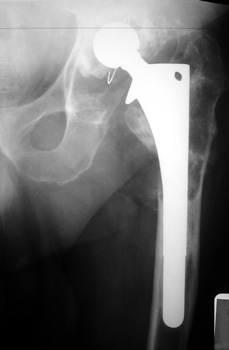

OSTEOLYSIS—Gruen zones 2 and 3, with markedly thinned femoral cortex, placing patient at risk for pathologic fracture